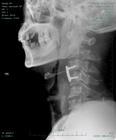

棘突骨折是指颈椎过屈所致。单纯棘突骨折较少见,常合并椎体或其他附件骨折。以c6至T1棘突多见。骨折常见铲土工和矿工,又称为铲土者骨折。猛烈屈曲下,颈椎棘突和肌肉对抗性牵拉造成棘突撕脱骨折。垂直压缩暴力也可致脊椎纵向劈裂骨折,致棘突沿矢状劈开,但此不常见。棘突骨折多发生在棘突基底部上方,骨折伴有棘间韧带和项韧带撕裂损伤不累及椎管和椎问孔。极少伴脊髓和神经根损伤。